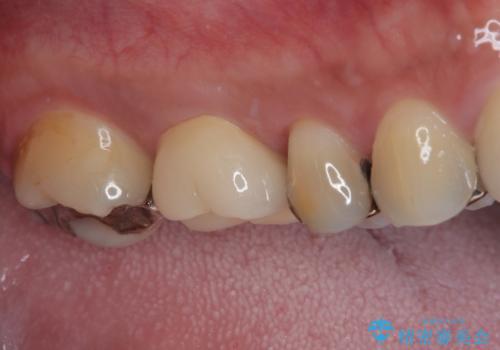

治療途中の奥歯 オールセラミッククラウンでのむし歯治療

- 近医にて治療を行っていたものの、痛みがなかなか引かないとのことで転院されてきた患者様です。

上下で接触しないように削られていたため、日常生活で痛みを感じることはありませんでしたが、歯を叩くと痛みを感じる状態でした。

前医ではラバーダムの装着をされていない状態で根管治療を行っていたようで、その他の器具や処置も無菌的環境下であったとは考えにくいため、それが痛みがなかなか引かない原因の一つであると考えられました。

根管治療後に痛みの消失を確認し、オールセラミッククラウンにて補綴治療を行うこととしました。